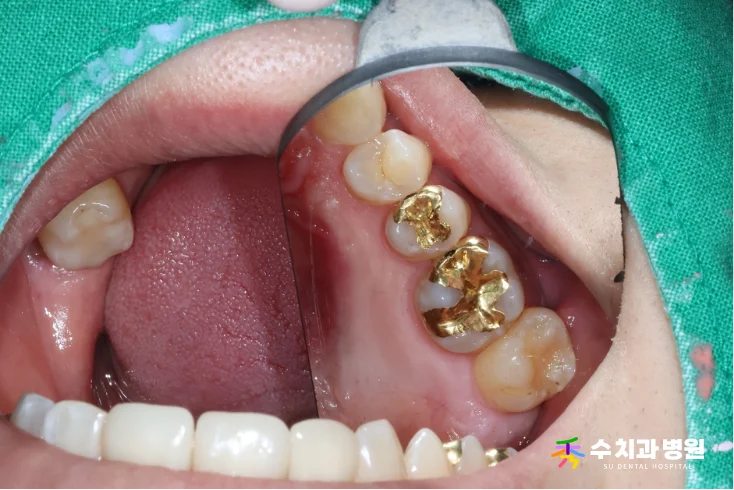

✨ 치료 후 (After)

치료 후 사진 (촬영일: 2022.07.04)

골드 인레이 치료가 잘 마무리되었습니다.

치아의 빈 공간에 정확하게 들어맞습니다.

깊었던 충치는 완벽하게 제거되었고,

강력한 씹는 힘을 견딜 수 있도록

치아의 기능이 튼튼하게 회복되었습니다.